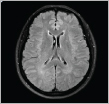

응급질환인 경우 외래에서 즉각적인 입원 치료로 연계될 수 있도록 도와 드립니다. 소뇌나 뇌간경색과 같은 중추신경계의 문제로 발생하는 어지럼증의 경우에는 뇌혈관 촬영을 포함한 머리자기공명영상검사 등을 아울러 진행합니다. 간혹 노인성 어지럼증의 경우 여러 감각 및 기억력 감퇴와 보행장애를 유발하는 신경계 퇴행질환의 증상으로서 매일 만성 어지럼증을 겪을 수 있습니다. 이러한 환자분들에게는 신경계 퇴행질환파트 전문 진료팀과의 긴밀한 협의 진료를 통해서 통합적인 진단 및 치료를 받을 수 있도록 노력하고 있습니다. 뇌신경센터는 모든 환자분들의 편안한 진료와 안전한 치료, 그리고 무엇보다도 빠른 쾌유를 기원 합니다.